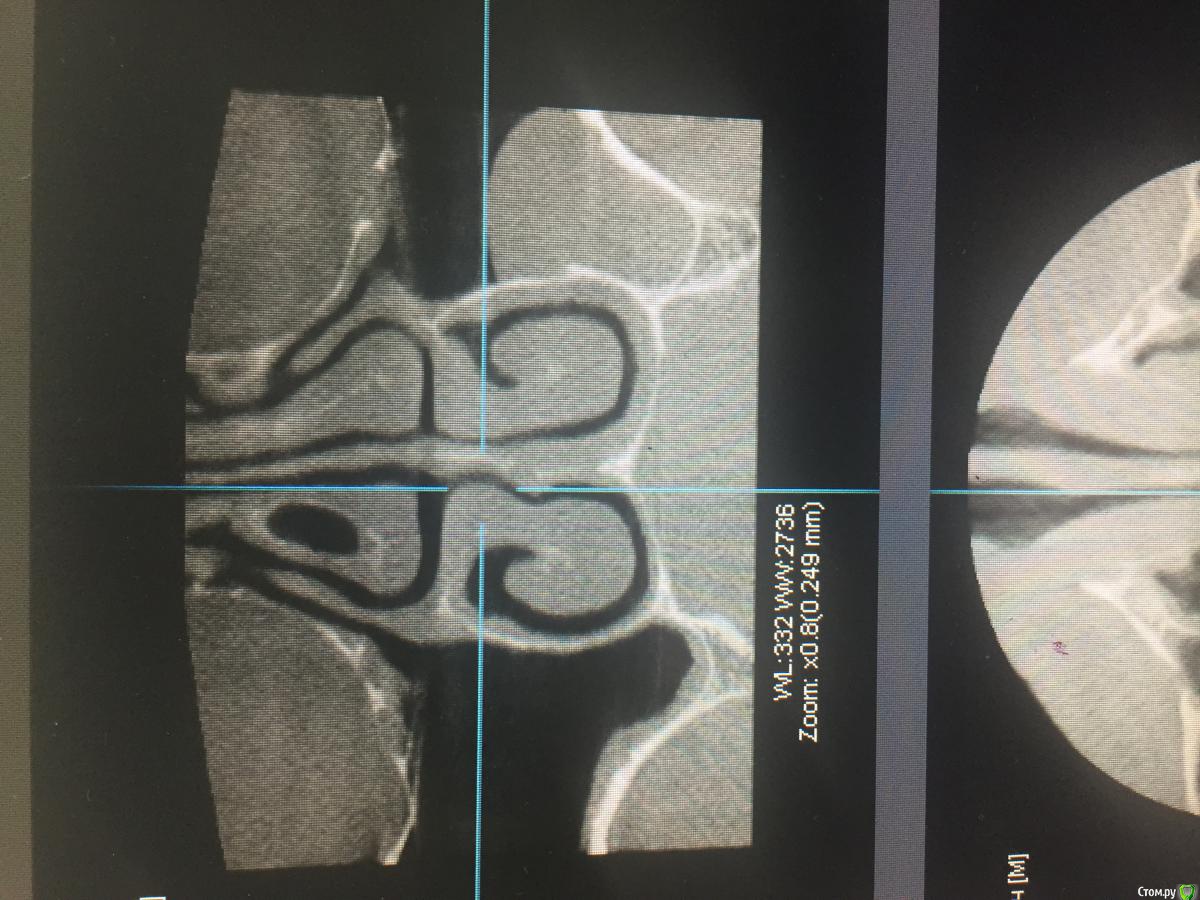

TIGER Опубликовано 26 октября, 2016 Поделиться Опубликовано 26 октября, 2016 (изменено) Доброго времени суток коллеги!Вот такая "штука " обнаружена на КТпричина тоже видна ,это 28 зуб...соустье в норме...вопрос:необходима установка имплантов и синус ,но и удаление 28 естественно...во время паботы в синусе как поступить с этим затаившимся злом?)у кого есть опыт?буду признателен ✌ Изменено 26 октября, 2016 пользователем TIGER Ссылка на комментарий

Nazim_NV86 Опубликовано 26 октября, 2016 Поделиться Опубликовано 26 октября, 2016 Добрый вечер. В передней стенке на уровне верхнего края кисты виден сосуд. Это первое. Кисту можно удалить и сделать синус лифтинг. Где то на форуме был кейс. Вы делаете два окна друг на другом. Через верхнее опорожняете и вылущиваете кисту. Через нижнее - синуслифт. Ссылка на комментарий